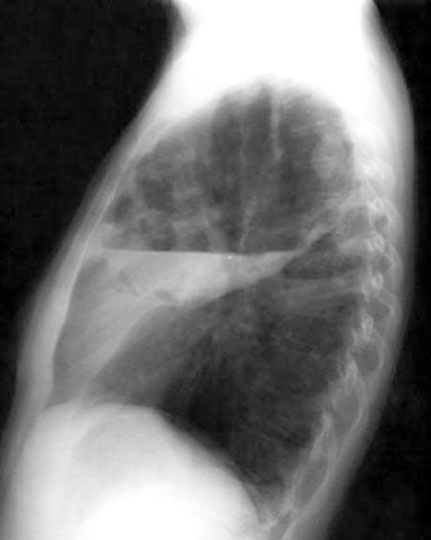

The x-ray on left is an example of lung abscess and tuberculosis.

LUL lung abscess

• Fluid level

• Necrotic mass along walls

RUL infiltrate: Tuberculosis

• This appearance can also come from branchiogenous spread of abscess contents to the right lung. AFB was positive in this case.